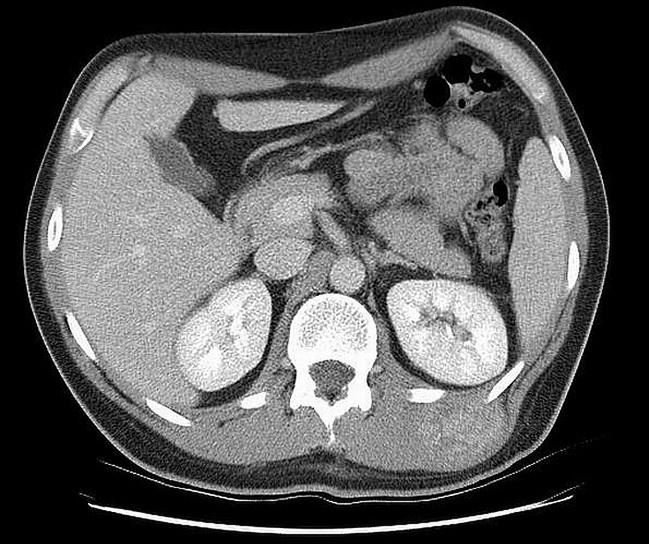

Guz Wilmsa to nowotwór nerki.

W sytuacji, gdy jego wynik nie jest jednoznaczny należy poszerzyć diagnostykę o urografię, badanie tomografem komputerowym lub rezonansem magnetycznym. Zalecane jest także wykonanie zdjęcia RTG klatki piersiowej lub tomografii komputerowej płuc, ponieważ nowotwór najczęściej daje przerzuty do tego narządu.